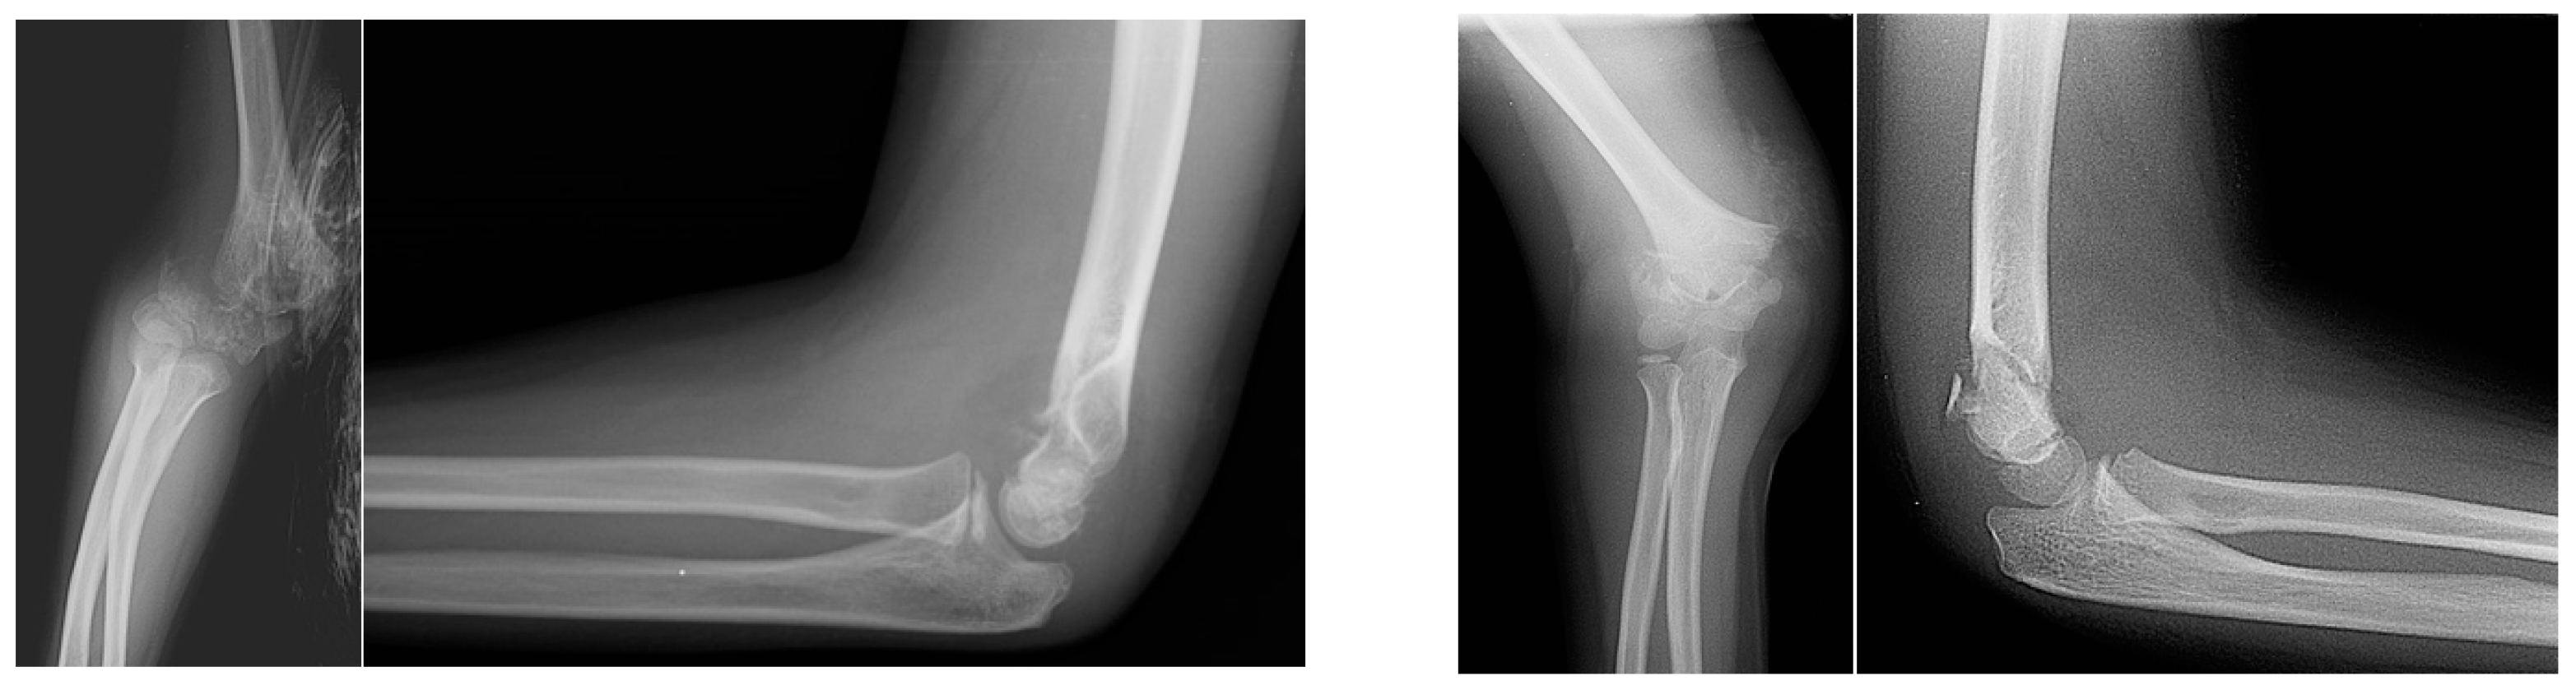

Supracondylar fracture Gartland 1. Download Scientific Diagram Supracondylar Fracture X Ray Lines Supracondylar fracture is seen on lateral radiograph with mild posterior displacement. Learn how to classify supracondylar fractures in pediatric patients using the gartland system, which has four types based on the degree of displacement and periosteal. Radiographic parameters are commonly used to determine the need for surgical supracondylar humeral (sch) fracture reduction. The anterior humeral line doesn't. Learn about the. Supracondylar Fracture X Ray Lines.

Xray showing Gartland type III supracondylar fracture of the humerus Supracondylar Fracture X Ray Lines Supracondylar fracture is seen on lateral radiograph with mild posterior displacement. The anterior humeral line doesn't. Learn how to classify, manage and follow up supracondylar fractures of the humerus in children, using the gartland system. Radiographic parameters are commonly used to determine the need for surgical supracondylar humeral (sch) fracture reduction. Supracondylar fractures of the humerus account for up to. Supracondylar Fracture X Ray Lines.